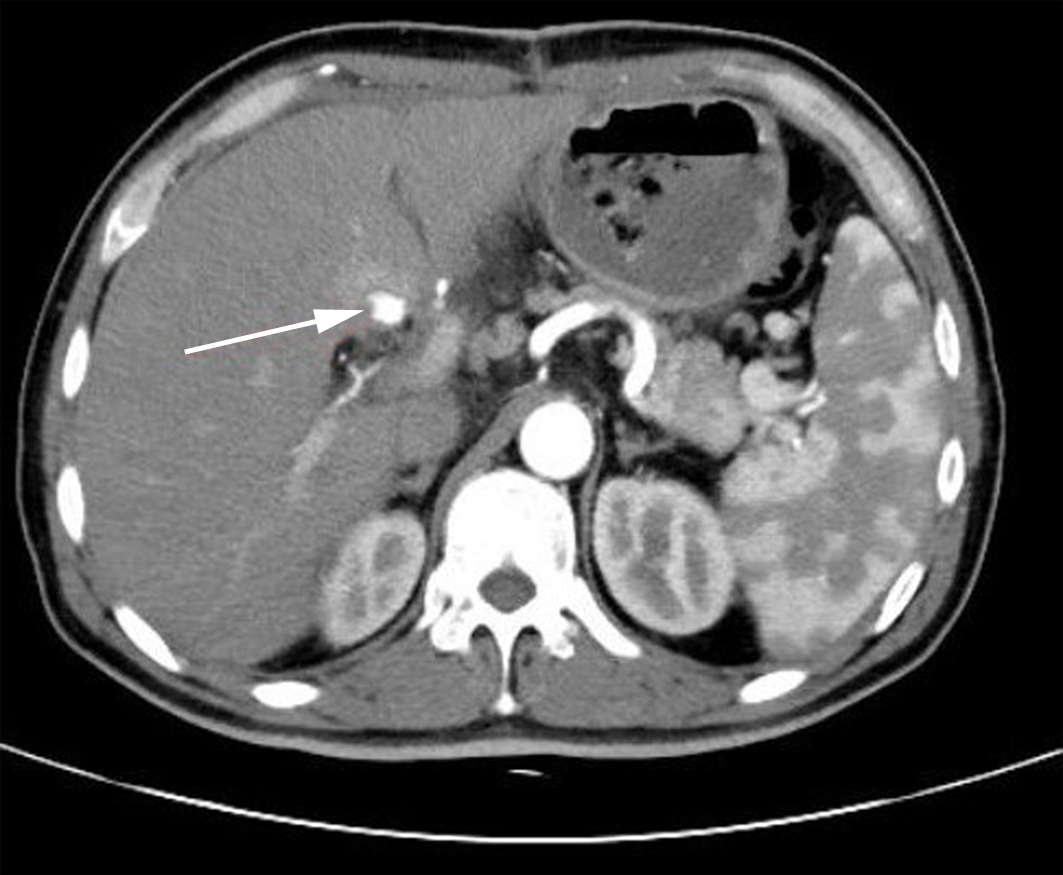

Diagnosis and treatment of hepatic pseudoaneurysm with bile leakage and bile duct hemorrhage after transplantation of donor liver with right hepatic artery variation: A case report

Tian HAN, Rui ZHANG, Zhiyong SHI, Li ZHANG, Jun XU

2022, 38(12): 2818-2820. DOI: 10.3969/j.issn.1001-5256.2022.12.024

Abstract(1759) HTML (1058) PDF (2268KB)(66)